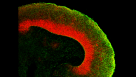

挂图Building Three-Dimensional Human Brain Organoids Overview of brain organogenesis and the applications of brain organoids in studying the development and maturation of the nervous system -